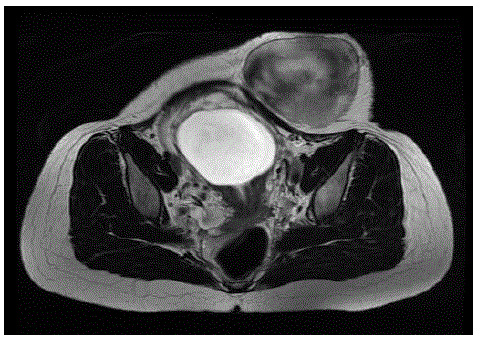

Mulher, 27 anos de idade, apresentou quadro de dor, com aumento progressivo de intensidade, e abaulamento em abdome inferior cerca de 3 meses após operação cesariana para parto do primeiro filho.

Ao exame físico, apresentava tumor de consistência pétrea em proximidade de cicatriz de incisão de Pfannenstiel, dolorosa, fixa, de cerca de 10 cm de diâmetro.

Realizada a seguinte ressonância:

Foi realizada biópsia através de punção por agulha grossa cujo exame anatomopatológico mostrou tratar-se de fibromatose do tipo desmoide.

Sobre o caso em questão, assinale a única alternativa correta: